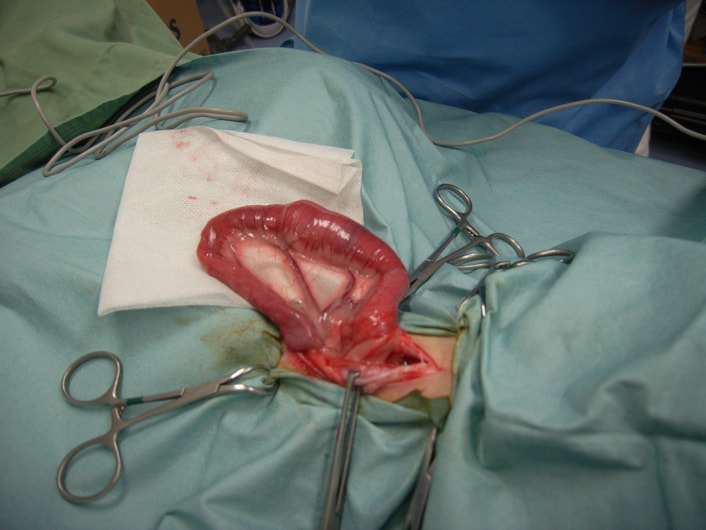

症例3:腸内異物(ヒモ状異物)

雑種猫 4歳 オス

主訴:2時間ごとの嘔吐

◎各種検査結果

・血液検査:著変なし

・レントゲン検査:腸内ガス陰影重度

・バリウム像影検査:造影後2時間、胃からのバリウム排泄なし上記検査結果より、内視鏡検査実施。

・内視鏡検査結果:胃内炎症性病変あり。胃の幽門部から十二指腸領域に向かいヒモ状異物確認。

内視鏡検査結果より、十二指腸領域へのヒモ状異物の可能性があるため、同日腸内異物摘出術実施。

腸内異物摘出術

腸管のアコーディオン様所見

腸内異物摘出

摘出した異物

今回の様なヒモ状の異物は、腸の蠕動運動により腸管を傷つけ、発見が遅れると腸穿孔などの重篤な状態を引き起こします。本症例は、術後1週間程で回復し、現在の経過は良好です。